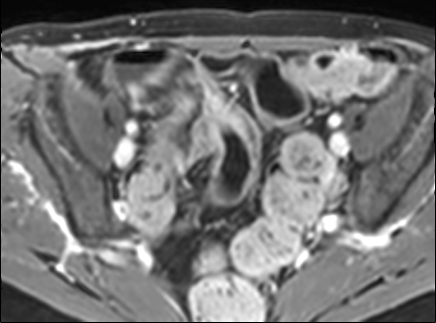

Bệnh nhân nữ 48 tuổi, đang điều trị bằng thuốc kháng TNF, được chỉ định nội soi đại tràng.

Phát hiện hẹp lòng ruột ở đại tràng sigma, không thể vượt qua được khi nội soi.

MR-enterography được thực hiện để đánh giá mức độ lan rộng của chỗ hẹp.

Cuộn qua các hình ảnh.

Ruột non bình thường, nhưng ghi nhận các đoạn hẹp ở đại tràng xuống và đại tràng ngang.

Cả hai đoạn hẹp đều có thành ruột dày đến 8 mm và ngấm thuốc rõ rệt theo kiểu niêm mạc ở đại tràng xuống và kiểu phân lớp ở đại tràng ngang.

Giãn ruột trước chỗ hẹp được ghi nhận ở cả hai đoạn.

Do các chỗ hẹp này không hiện diện khi nội soi đại tràng trước khi điều trị kháng TNF, nhiều khả năng chúng đã hình thành trong quá trình điều trị.

Do đó, quyết định phẫu thuật cắt đại tràng gần toàn bộ với miệng nối hồi-sigma đã được đưa ra.